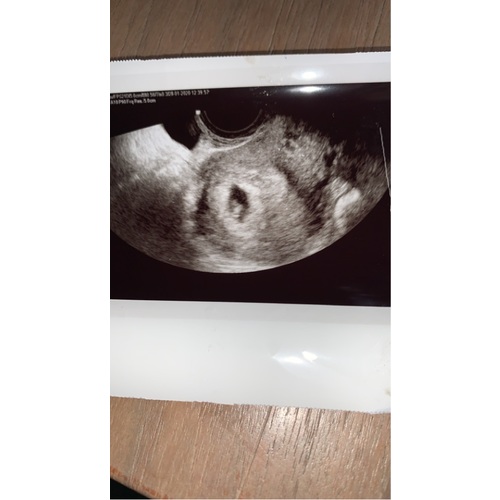

Eerste echo was 180, check erna met doppler was 160, en 2e echo was volgens ...

Het hartje is waarschijnlijk net op gang en dan is deze wat lager. Vaak laten ze het dan ook niet horen/ziet.